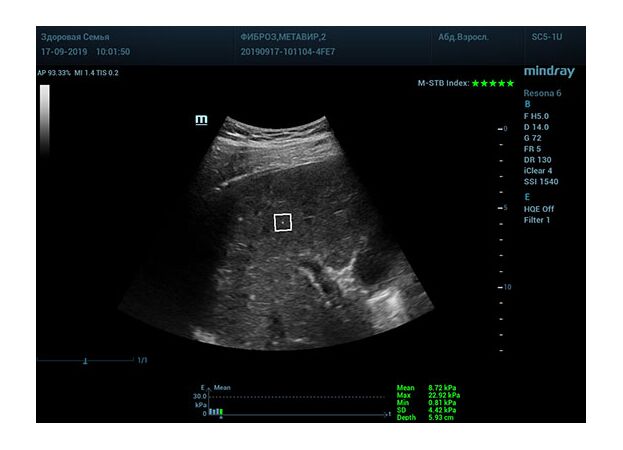

Определение плотности печени. Не ошибся ли оператор при измерении эластических свойств печени? Для оценки критериев качества предусмотрен индекс MBT, который покажет насколько «твердой» была рука оператора и двигалась ли печень. При MBT 5* рука тверда и показатели достоверны. Для оценки качества результатов используется IQR индекс, отображающий колебания показателей в точке измерения при расчете медианы. Показатели при IQR <30% считаются приемлемыми. Техника сканирования через межреберные промежутки требует размещение окна интереса на несколько сантиметром ниже капсулы, для исключения эффекта реверберации. Установка ROI на паренхиму без захвата сосудов, для исключения погрешностей измерения.

Стадия фиброза определяется по системе METAVIR Staging, построенной на данных биопсии и сопоставлении с данными эластографии. Своевременная диагностика фиброза, и начало его лечения, залог благоприятного исхода заболевания.

• METAVIRF2 – Портальный фиброз с вовлечением нескольких перегородок